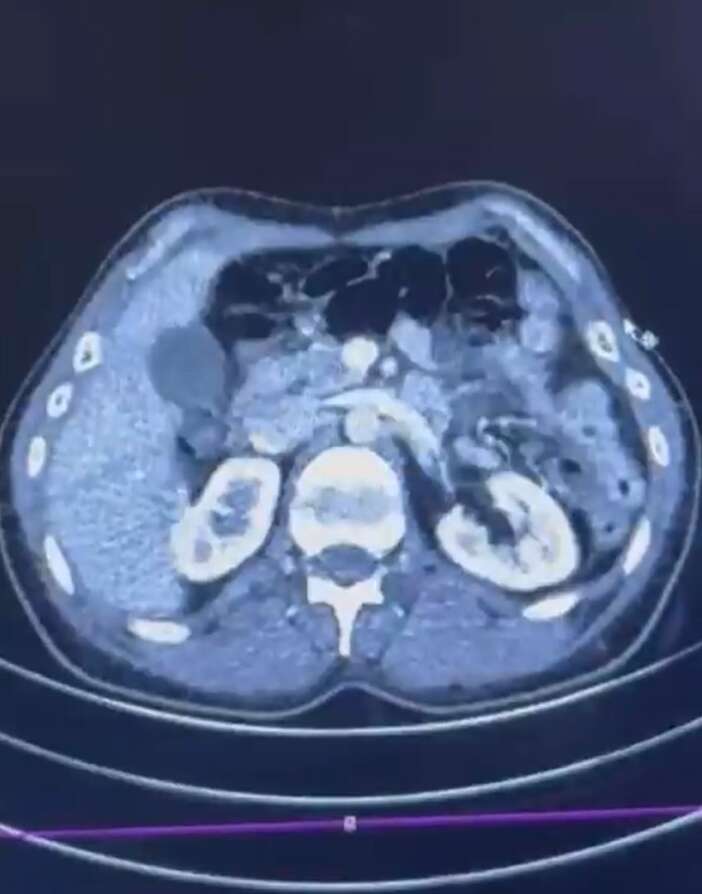

Ekipler, İran’dan Türkiye'ye uyuşturucu madde getirdiği tespit edilen şüpheli şahısların yakalanması amacıyla operasyon düzenlendi. Düzenlenen operasyonda; S.C., R.B.C. ve G.M. yakalandı. S.C. ve R.B.C.'nin Kayseri Şehir Hastanesi'nde yapılan iç beden muayenelerinde, mide kısımlarında bulunduğu tespit edilen 50 adet kapsül şeklinde toplam 554 gram uyuşturucu madde ele geçirildi.